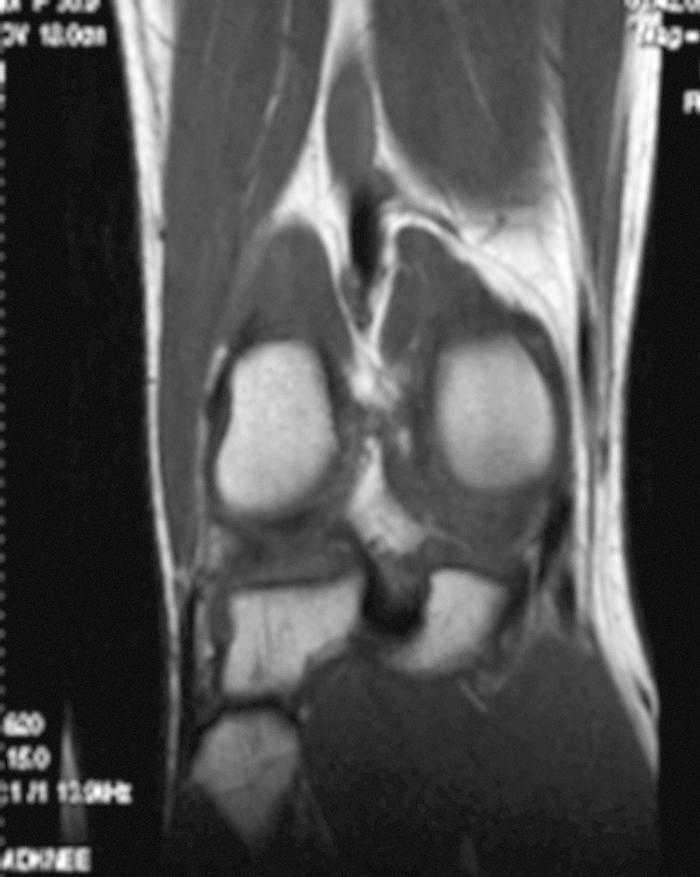

L'RM mostra (figs. 1, 3 i 5):

Figura 5 RM. Imatge potenciada en T1. Cossos lliures al voltant dels lligaments encreuats i en altres localitzacions intraarticulars.